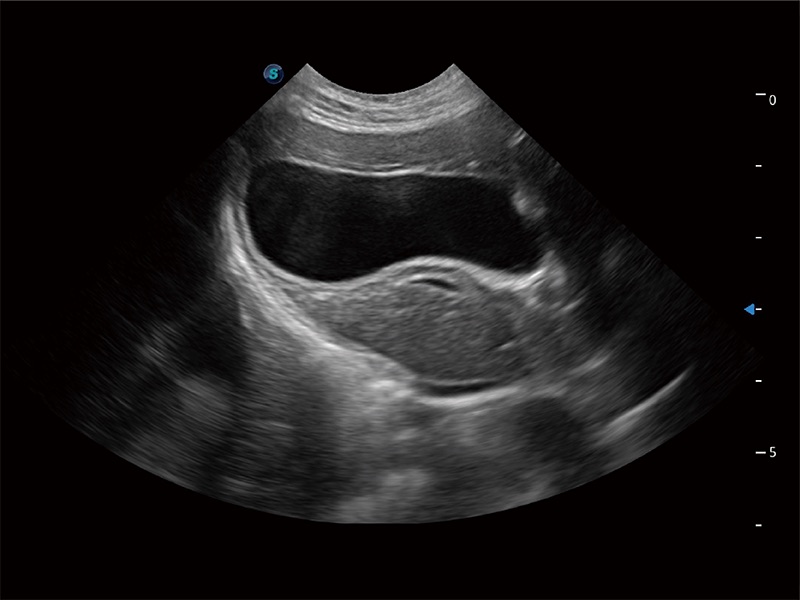

高性能和先进的临床应用工具可以为动物医生提供临床信心。ProPet 80 搭载了先进的腹部和浅表应用工具,帮助医生在日常临床实践中发挥前所未有的作用。

一键自动识别膀胱壁及自动测量膀胱容积,不受膀胱形状和大小的限制,帮助医生快速精准获得测量的数据。